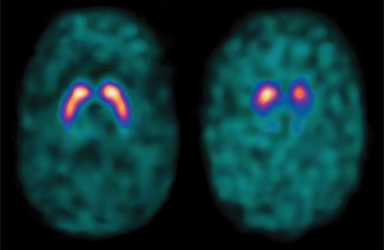

DaTscan™ Imaging

DaTscan™ provides detailed images of dopamine activity within the brain, which helps us differentiate between various Parkinsonian syndromes as well as between Parkinson’s disease and essential tremor—diseases that often share similar symptoms.